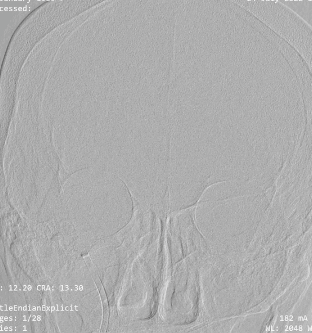

右侧颈内动脉造影示:后交通动脉以上颈内动脉闭塞。

术前正位造影。